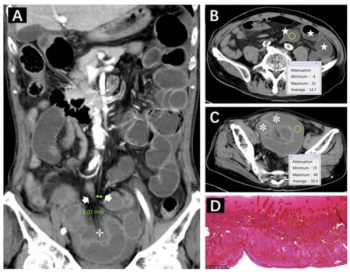

Demonstrating an 81 percent AUC, 99 percent specificity and a 98 percent positive predictive value, increased attenuation of intestinal contents was one of four CT findings deemed to be an independent predictive factor for bowel necrosis in patients with closed-loop small bowel obstruction.